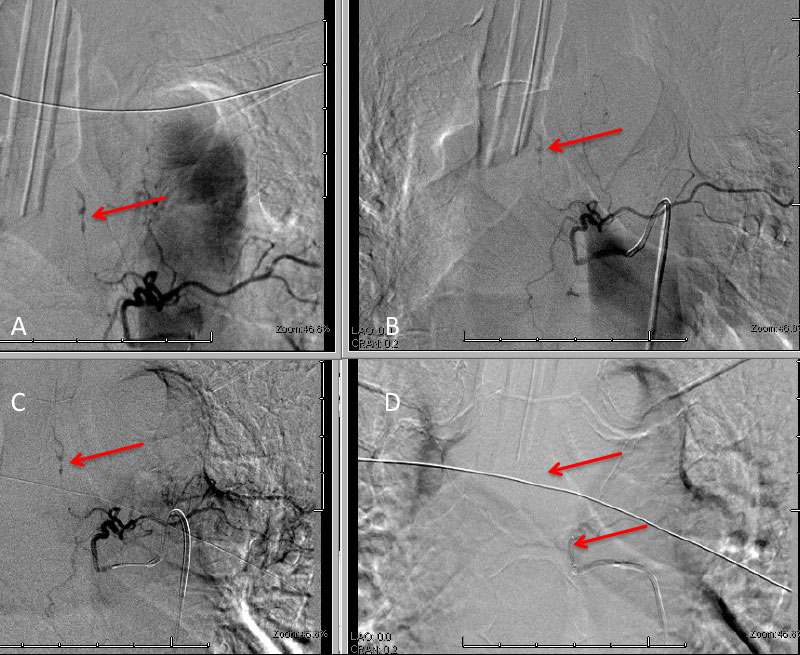

The subararachnoid hemorrhage was focused primarily within the spinal axis of the cervical thoracic and lumbar spine with secondary extension into the brain. A suspicious focal hematoma or mass was observed within the left T4-T5 region with local mass effect representing an intradural extra medullary abnormality with secondary compression of the cord and central myelopathic T2 signal abnormality (Figure 2. A,B,C,D).

Figure 2: A) T1 B) C+ T1 C) STIR D) FS C+ T1 demonstrate focal hemorrhage, contrast enhancement, mass effect, and myelopathic cord signal at T4 (arrows)